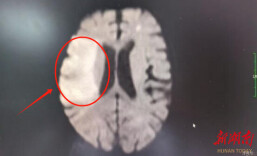

祁东县人民医院:康复医学点亮生命希望